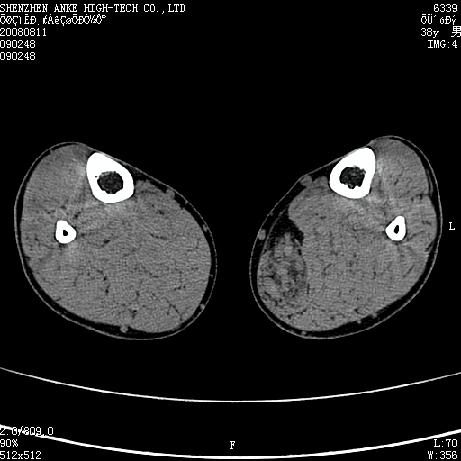

标题: CT15117:M38Y,小腿平扫 [打印本页]

标题: CT15117:M38Y,小腿平扫

患者,男,38岁,右小腿疼痛性包块1月,查体:右小腿可扪及约5x4cm大小包块,压痛.

左小腿内侧软组织病变,性质待定(血管瘤?);建议行mri检查。